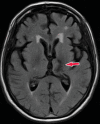

Neurodegenerative diseases are a devastating group of disorders that can be difficult to accurately diagnose. Although these disorders are difficult to manage owing to relatively limited treatment options, an early and correct diagnosis can help with managing symptoms and coping with the later stages of these disease processes. Both anatomic structural imaging and physiologic molecular imaging have evolved to a state in which these neurodegenerative processes can be identified relatively early with high accuracy. To determine the underlying disease, the radiologist should understand the different distributions and pathophysiologic processes involved. High-spatial-resolution MRI allows detection of subtle morphologic changes, as well as potential complications and alternate diagnoses, while molecular imaging allows visualization of altered function or abnormal increased or decreased concentration of disease-specific markers. These methodologies are complementary. Appropriate workup and interpretation of diagnostic studies require an integrated, multimodality, multidisciplinary approach. This article reviews the protocols and findings at MRI and nuclear medicine imaging, including with the use of flurodeoxyglucose, amyloid tracers, and dopaminergic transporter imaging (ioflupane). The pathophysiology of some of the major neurodegenerative processes and their clinical presentations are also reviewed; this information is critical to understand how these imaging modalities work, and it aids in the integration of clinical data to help synthesize a final diagnosis. Radiologists and nuclear medicine physicians aiming to include the evaluation of neurodegenerative diseases in their practice should be aware of and familiar with the multiple imaging modalities available and how using these modalities is essential in the multidisciplinary management of patients with neurodegenerative diseases.©RSNA, 2020.